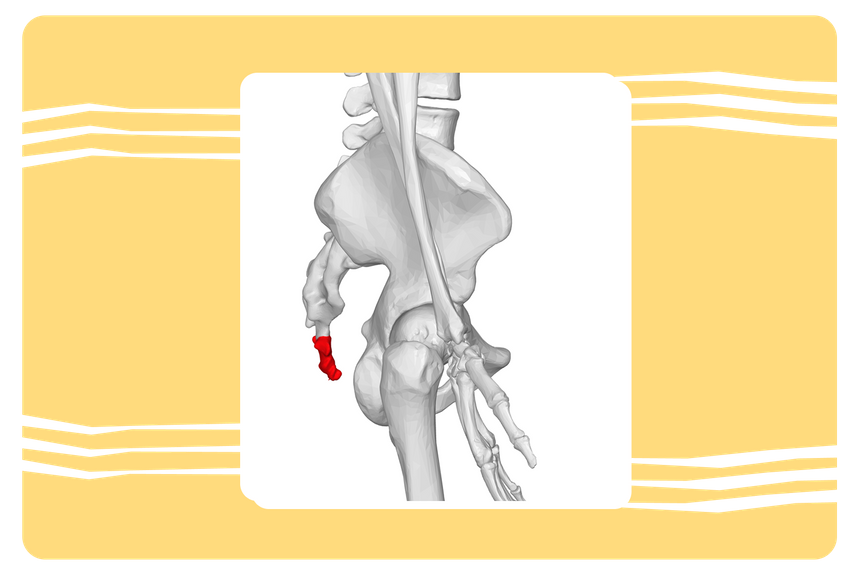

7. Копчик

Что это:

Нижний отдел позвоночника из 3–5 сросшихся позвонков. По сути, это рудимент хвоста, который был у наших предков миллионы лет назад.

Зачем требовался

Хвост помогал сохранять баланс при движении, выражать эмоции и служил «пятой конечностью» — дополнительной опорой при лазании по деревьям.

Что с ним стало сейчас

Со временем хвост исчез, а его «корень» — копчик — остался. Сейчас он выполняет важную роль: к нему крепятся связки и мышцы тазового дна, он участвует в распределении нагрузки при сидении.

Хвост у человека появляется при формировании в утробе матери. У эмбриона маленький хвостик сохраняется до 8–9-й недели, а потом пропадает. Однако в очень редких случаях он остается вплоть до рождения, после которого его удаляют хирургически.